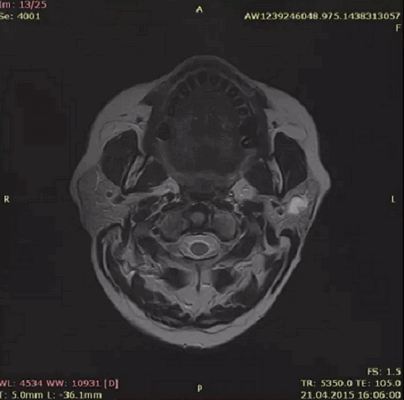

КТ-проявления болезни Шегрена

Аутоиммунное поражение железистой ткани сопровождается симметричным изменением органов (с обеих сторон). Использование КТ-сиалографии позволяет выявить специфические проявления нозологии:

- Зернистость поднижнечелюстной и околоушной железистой ткани;

- Снижение плотности;

- Шейная лимфаденопатия;

- Псевдолимфомы;

- Уменьшение размеров слюнных желез.

К аутоиммунному поражению может присоединяться бактериальная или грибковая инфекция околоушно-жевательной области. Томограммы показывают аналогичные нарушения жевательной мышцы, крыловидного пространства, поднижнечелюстной полости.